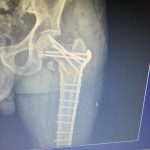

تعویض مفصل زانو و لگن

– شکستگی و در رفتگی

– از بین رفتن مفاصل